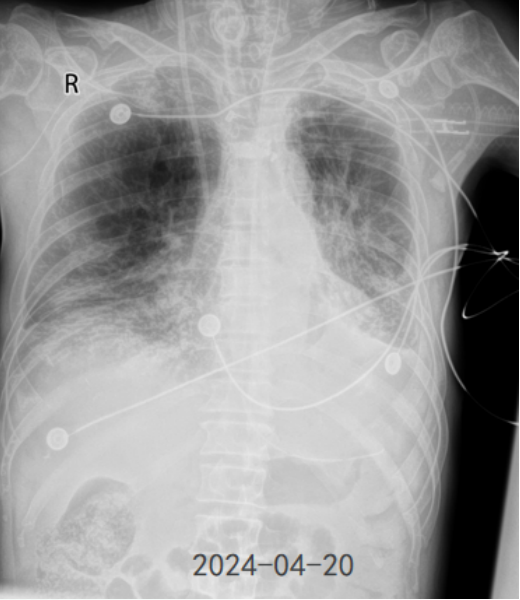

• 影像学:2月24日胸片提示右肺下叶病变,2月25日胸片可见病变范围迅速扩大(图3)

3  复查胸片对比